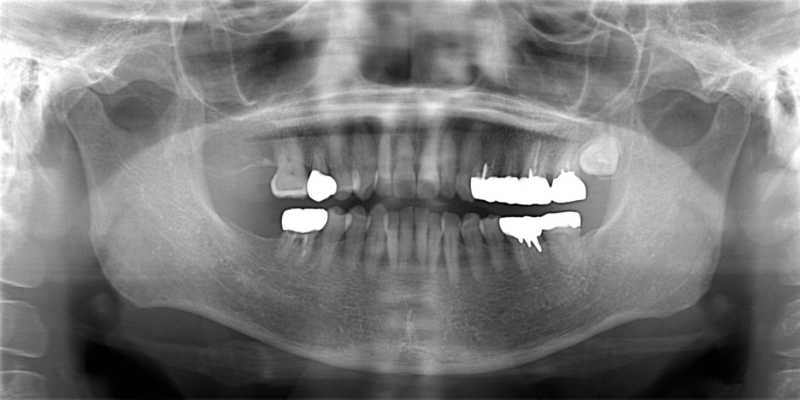

右下の一番奥の歯が痛むということで来院されました。右下は歯が割れており(歯根破折)、抜歯してインプラント治療を行いました。 CT所見から骨が比較的あったので、歯を抜くと同日にインプラント埋入オペを行いました。

患者様は64歳であり、ご自身の年齢と体力を心配されていましたが、問題なくインプラント治療を終えることができました。 インプラント手術は1回法と2回法とがありますが、今回は1回法を選択したため、オペに際する精神的肉体的な負担も最小限にすることができました。